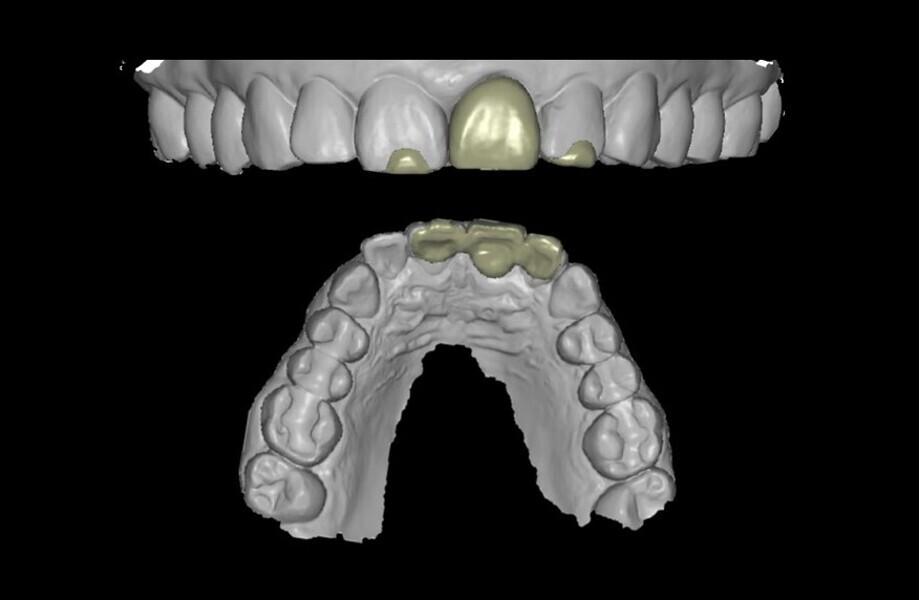

Fig. 20: Temporary crown designed in coDiagnostiX (Dental Wings).

Fig. 21: Temporary crown milled in PMMA.